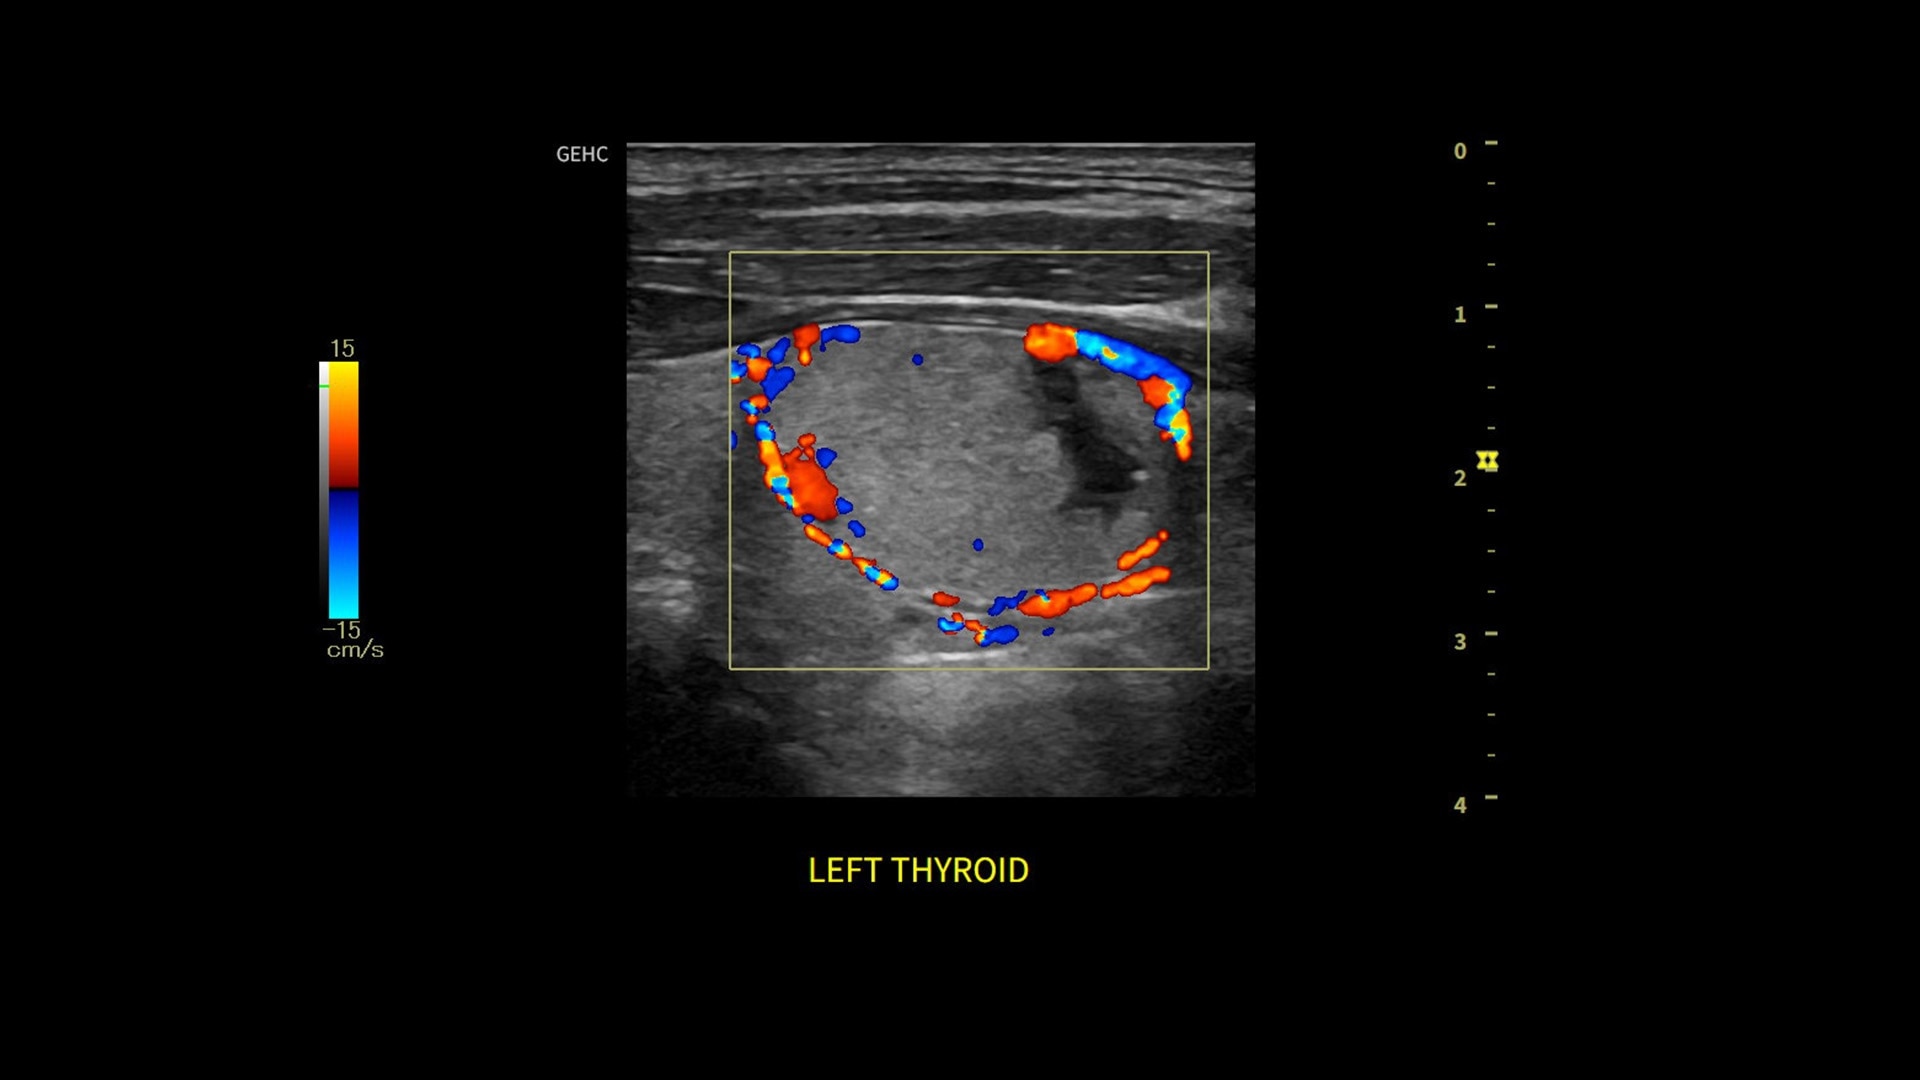

Powered by VisionBoost Architecture, Versana Premier provides optimal image quality so users can easily reach a diagnosis. Advanced clinical features help address challenging cases while automated tools help reduce scan time:

• Optimize images while scanning with Whizz clinical features, easily improve Color Doppler with Whizz Color Flow, and view scans in the image style that suits your preference with Whizz Easy Style

• Use automated labeling in the RUQ with Whizz Label

• Make automated 2D Measurements and Volume Calculations with Auto Contour, Auto Bladder, Whizz Follicle and Auto-IMT

• Assess liver, thyroid and breast nodules with Productivity Packages leveraging LI-RADS,® TI-RADS® and BI-RADS® criteria*